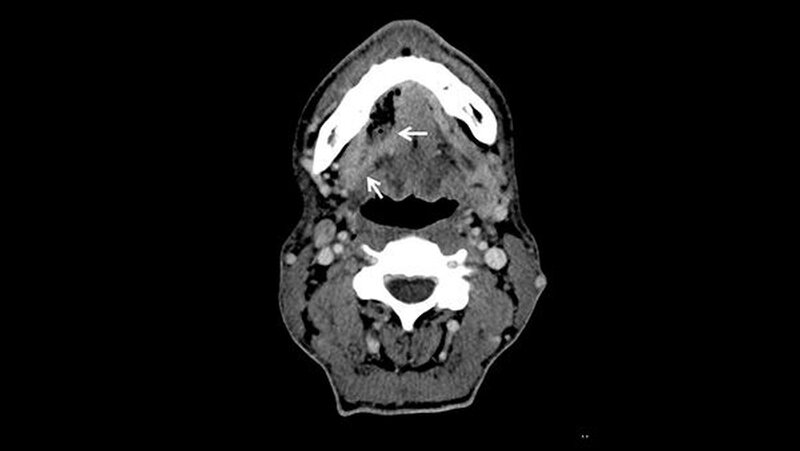

Weder das Röntgenbild noch die weitere Untersuchung mit magnetresonanztomografischer Bildgebung gaben eindeutigen Aufschluss. Daraufhin wurde eine Biopsie veranlasst, die die Verdachtsdiagnose einer Metastase des oralen Plattenepithelkarzinoms histologisch bestätigte.